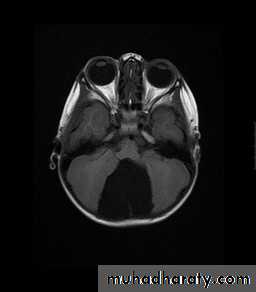

Chiari malformation:

Normally up to 5mm of tonsillar descent through the foramen magnum.

Chiari I: >5 mm of tonsillar descent.

Chiari II: descent of the tonsils and cerebellar vermis.

Chiari malformation Type II

Developmental Abnormalities of the Nervous System